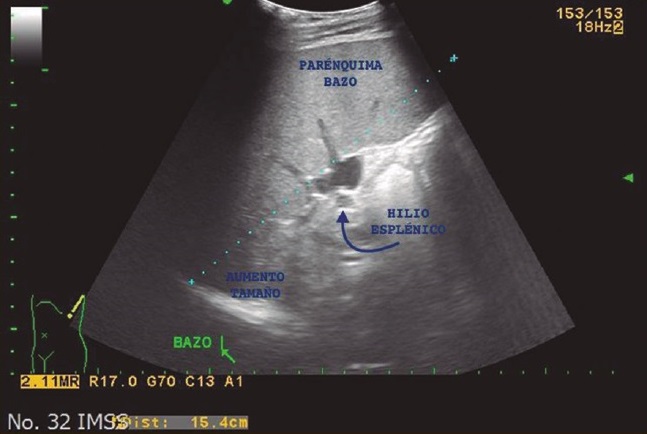

Fue enviado a la consulta externa del servicio de cirugía general por falla en el tratamiento médico. Como parte del protocolo preoperatorio, se solicitaron ultrasonido abdominal (figura 1) y tomografía axial computada (figura 2) para determinar las características anatómicas de bazo, además de estudios de laboratorio, se reportó una cifra preoperatoria de plaquetas de 27,000/mm3. Se decidió intervención quirúrgica de forma programada con plan de esplenectomía laparoscópica. Se solicitó valoración por el servicio de infectología para la aplicación de vacunas contra bacterias encapsuladas, las cuales fueron aplicadas 48 horas posteriores a la cirugía.

Imagen: otorgada por los autores

Figura 1 Ultrasonido abdominal de paciente con PTI y esplenomegalia